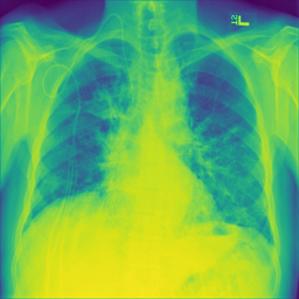

Neural network models are often described as inscrutable systems because understanding the reasoning behind their predictions is challenging. This is where Explainable AI (XAI) becomes important; XAI helps us understand how these models make decisions. In this study, LIME as our explainable AI method. created by Ribeiro et al[27]. LIME can explain how any classifier or regressor works, no matter how complex. It does this by approximating the model locally to something simpler and easier to understand, making the reasons behind the model’s predictions clear. This way, LIME helps bridge the gap between complicated machine learning models and the people using them, providing valuable insights into why the models make certain decisions. Figure4 shows how LIME explains a model’s misclassifications of chest X-rays. Lung Opacity is the actual label; Viral Pneumonia is what the model predicted. LIME indicated in green the regions with Viral Pneumonia and in red the other classes in the first plot. The second set of plot displays LIME highlighting in green the regions that belong to Normal and in red other classes. LIME highlights in the third set regions that indicate Covid in green and other classes in red. LIME indicated in the fourth set the regions that correspond to Lung Opacity in green and the other classes in red.

Refer to caption

Figure 4: Some Sample Images of Actual Class Predicted Incorrectly by TL Model

LIME’s predictions can be understood by examining the highlighted areas in green and red. The green areas represent the actual regions for which the model predicts the given class, while the red areas correspond to other classes. In the fourth plot, the green area for Lung Opacity is the largest compared to the green areas in the other three plots. This is why the model predicted Lung Opacity, even though the true label is Viral Pneumonia. The larger green area indicates that the model’s decision is primarily influenced by these regions, showing that the model focuses more on features associated with Lung Opacity. By analyzing these highlighted areas, we can understand why the model made its predictions, revealing the reasons behind the black box of the model’s predictability and helping identify potential misclassifications. This analysis helps us see how the model might be misled by certain features, emphasizing the importance of examining these explanations to improve model accuracy and reliability.